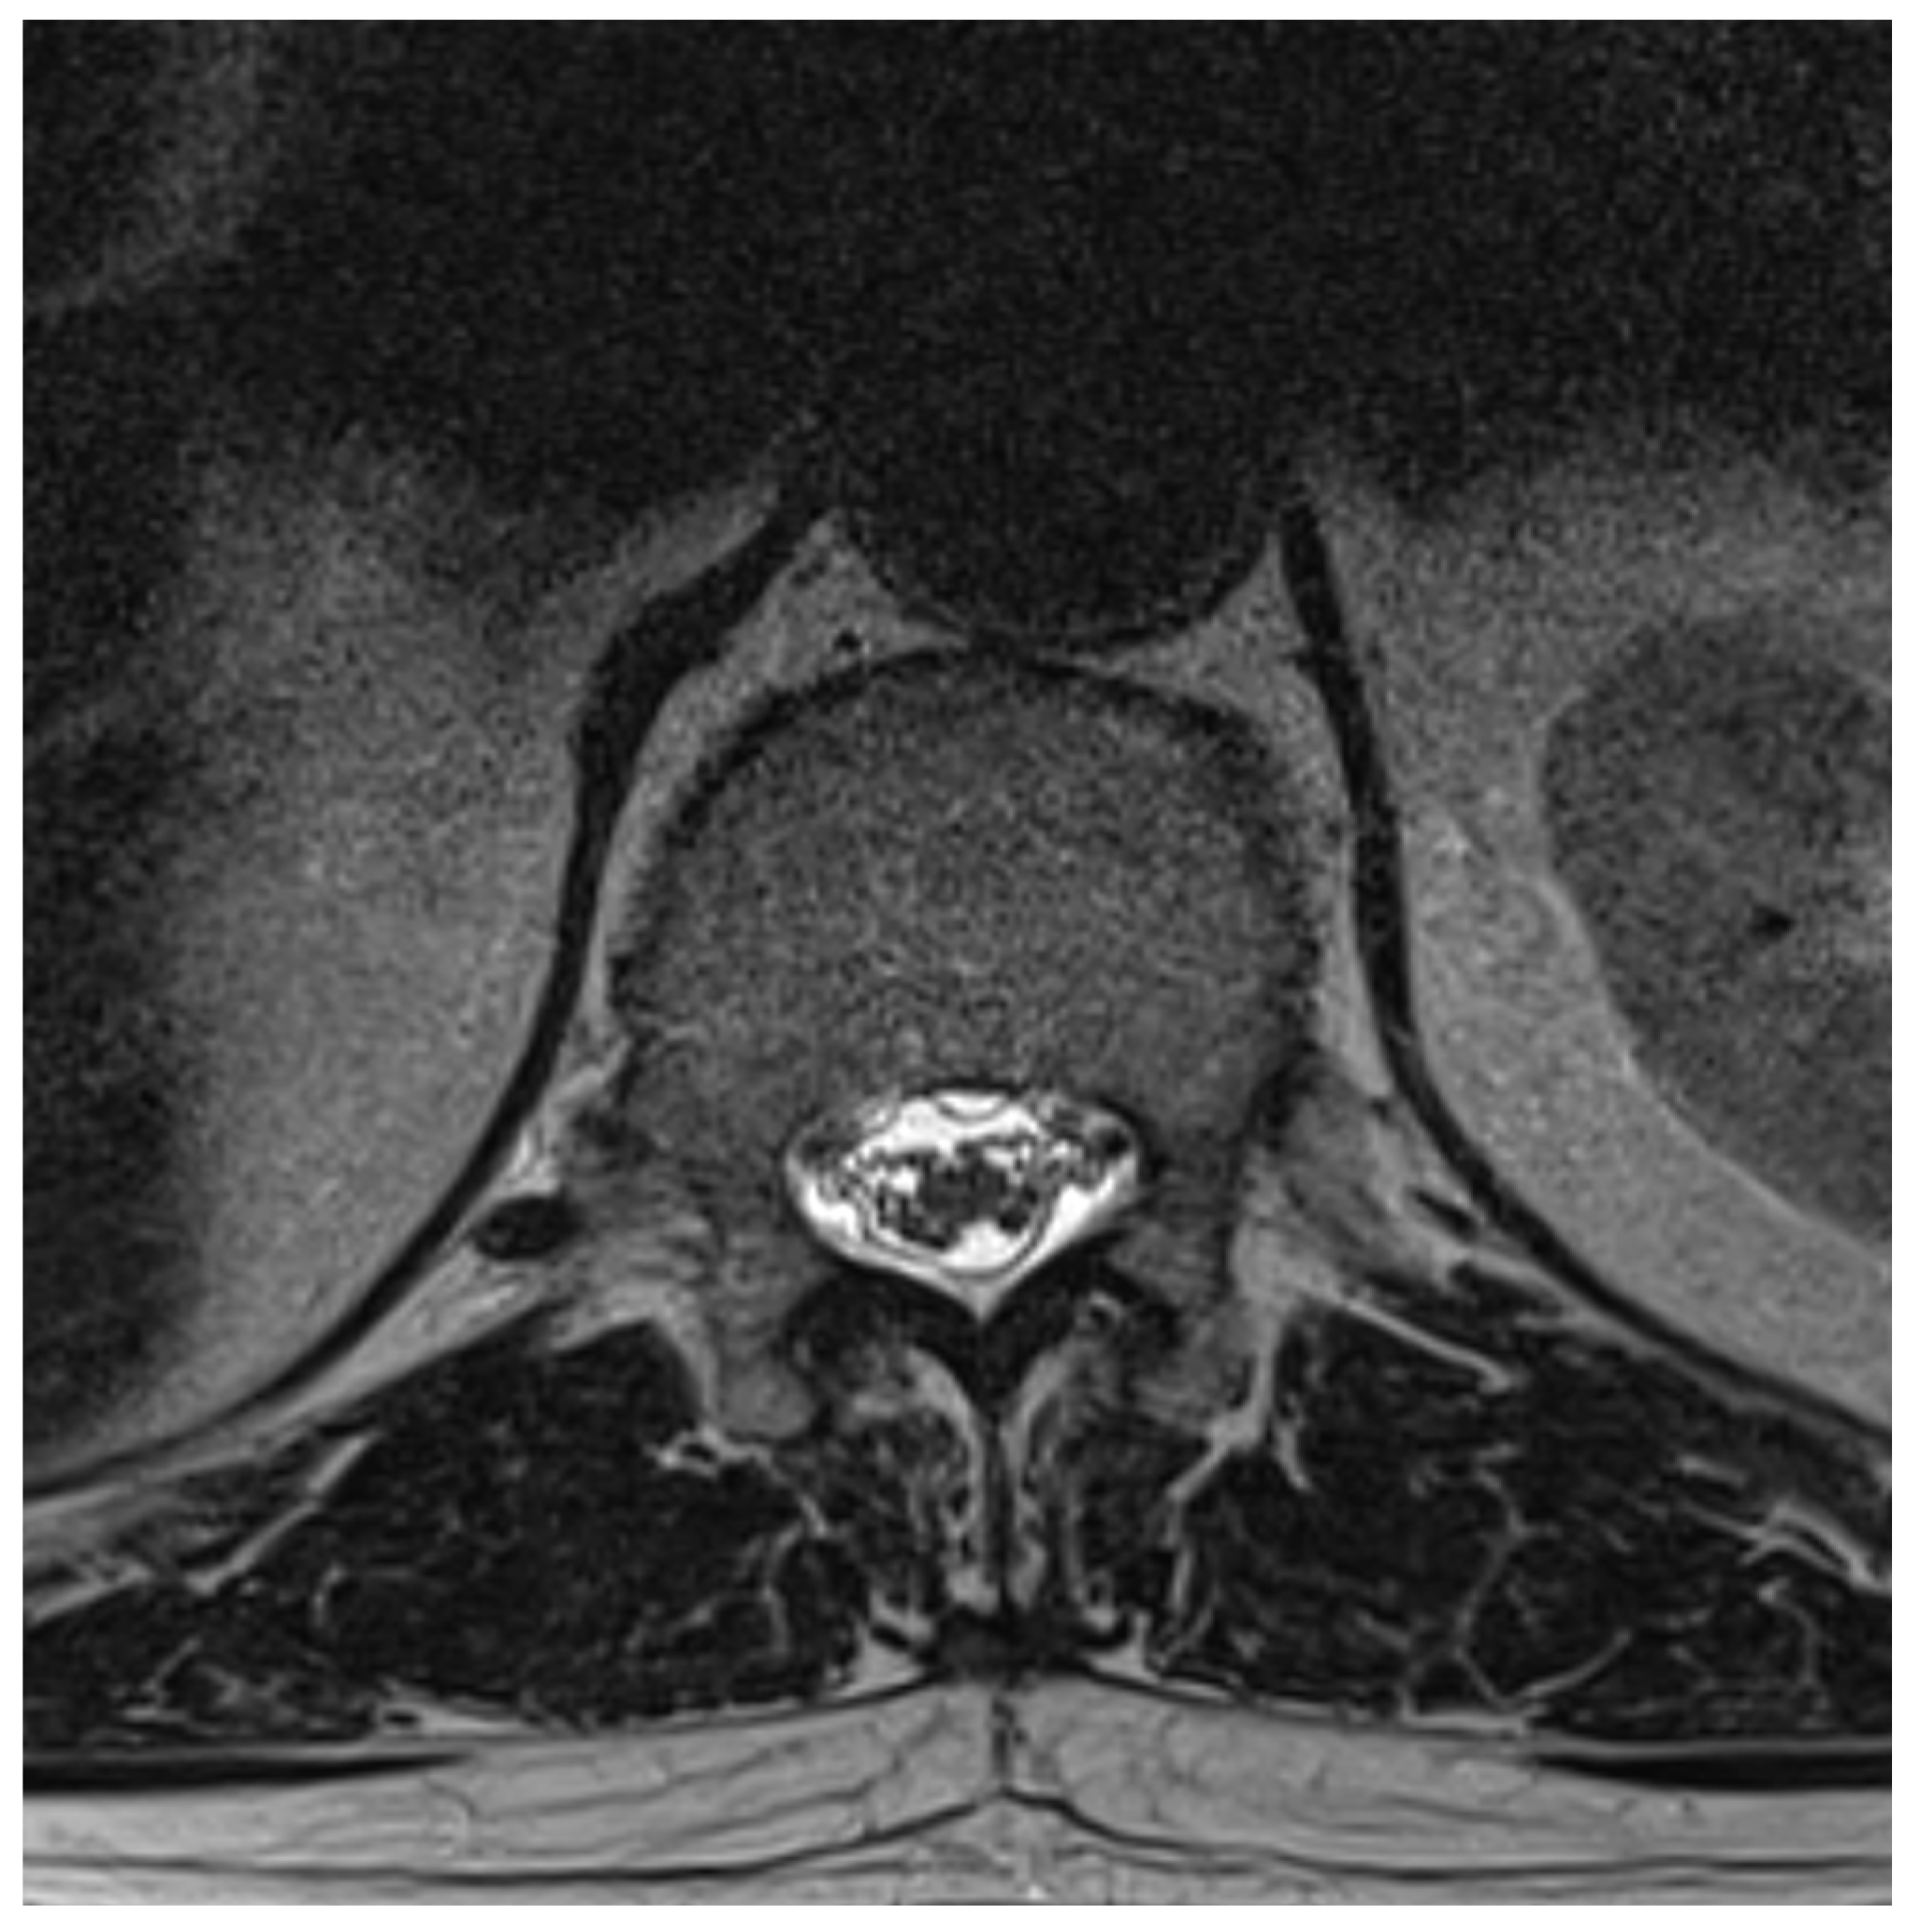

Among the 722 punctures, complications occurred in four cases (0.6%), see Table 3. Three of these complications arose after the first administration and one after the second. Reported complications included one case of post-puncture aggravation of pain, and one case of post-puncture headache. Both cases were managed conservatively using analgesics. In one case, shortness of breath occurred. In this patient, a cardiopulmonary event was ruled out, which required performing blood sampling as well as a CT-angiography of the pulmonary arteries. In another case, an intracranial subdural hygroma occurred, see Figure 2. No neurological deficits occurred, but due to persistent headache, an MRI scan was performed which revealed the diagnosis. The patient was readmitted for inpatient treatment for another 5 days 1 month after initial puncture. An MRI scan of the lumbar scan revealed epidural accumulations of cerebrospinal fluid at the thoracolumbar junction (Figure 3). Bed rest was ordered for 3 days. 2 days after readmission, a CT-guided lumbar blood patch was performed at the level L2 with 35 mL of blood, and oral analgesics were administered. The patient was discharged after five days. At subsequent follow-up visits, the patient reported no further headaches, and an MRI performed six weeks later demonstrated the complete resolution of the epidural cerebrospinal fluid collections (Figure 4).

Figure 2. Axial T2 MRI, showing subdural hygroma on the right side. The image was acquired 1 month after intrathecal injection due to persistent headache.